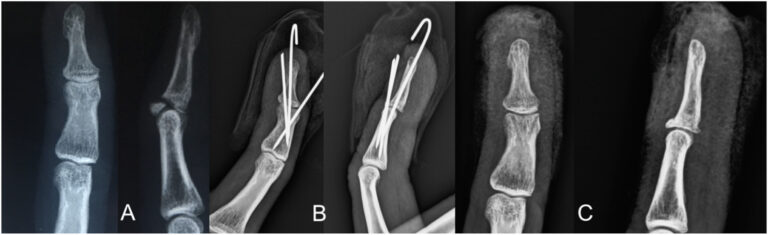

La colocación de clavos en bloque de extensión percutánea es una de las modalidades de tratamiento para las lesiones óseas desplazadas en martillo. Se han descrito varias modificaciones técnicas con una o más agujas de Kirschner. El propósito de este estudio es analizar los resultados de la fijación con alambre de Kirschner dorsal específico de un fragmento para las fracturas en martillo.

- Sugerimos la primera aguja de Kirschner como paso clave para la reducción de fragmentos de fracturas.

- Aguja de Kirschner de lados radiales para desplazamiento dorso-radial.

- Un lado cubital para el desplazamiento dorso-cubital.

- Dos agujas de Kirschner dorsales paralelas para el fragmento central.